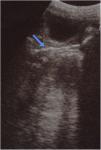

No había antecedentes de traumatismo, abuso sexual, dolor o problemas urinarios o rectales. Los síntomas no respondieron a las medidas de higiene ni a tratamiento antibiótico. En la exploración física no se apreciaba dolor abdominal y los genitales eran normales, sin lesiones ni secreción activa de flujo. No obstante, se observó secreción maloliente y sanguinolenta en la compresa de la paciente. La ecografía (fig. 1) y la radiografía (fig. 2) pélvicas revelaron la presencia de un cuerpo extraño de 40×10mm. La paciente fue sometida a vaginoscopia bajo anestesia con objeto de extraer una horquilla.